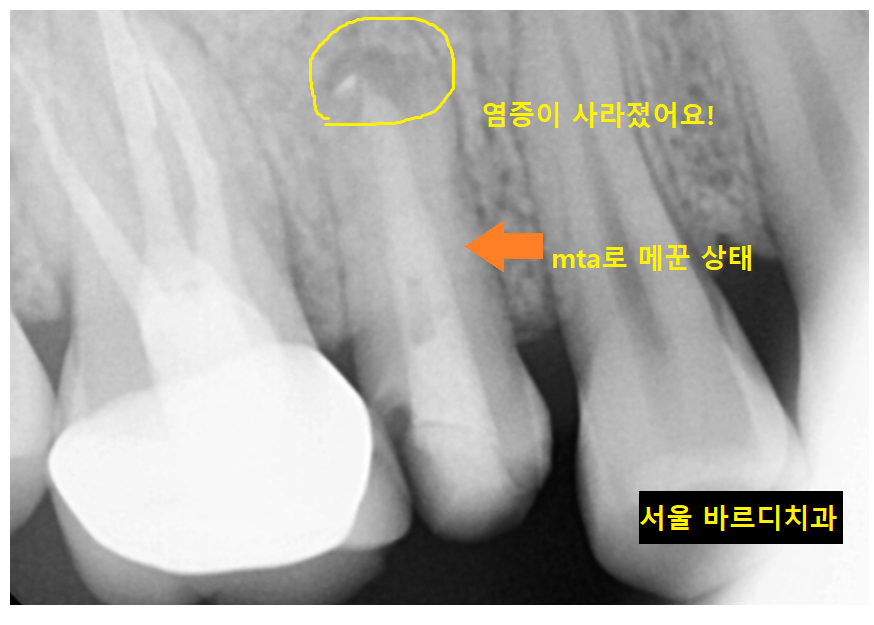

더이상 염증이 안나올때쯤...

비장의 무기 mta를 사용해서 치료롤 마무리 했습니다.

MTA는 Mineral Trioxide Aggregate의 약자입니다.

이 재료는 기존 사용되던 재료에 비해

감염성을 낮춰주고

재생 효과도 높습니다.

내 치아의 신경과 성분이 비슷해요~

염증 조직을 제거해주면서

내부를 밀폐해 다시 감염될 가능성도 낮춰주는데요.

고가의 재료이긴 하지만

환자분을 위해서는

기꺼이 팍팍 아끼지않고 사용합니다!!

23.10.15

기존 재료를 제거하고

mta로 재신경치료 마무리 한 모습입니다.

처음 망월동 치과 방문하셨을 때는

뿌리 끝이 검정색으로

염증이 있는 상태였는데

많이 줄어든게 보이실껍니다.

한장으로 전후 차이 보여드릴께요~

뿌리 끝 검게 잡힌 염증도

재신경치료 후

싸악 사라졌습니다!!